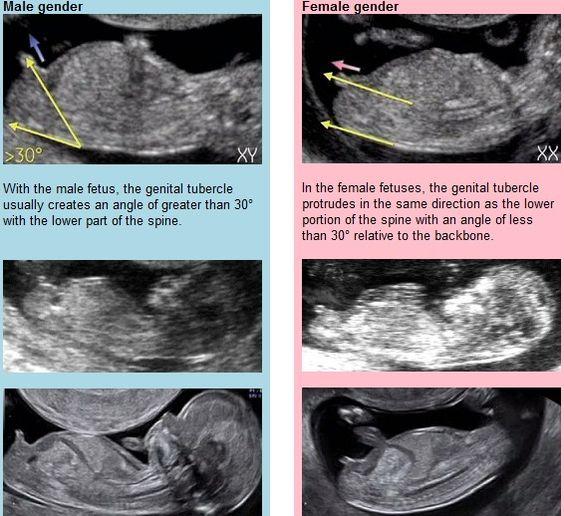

Za mě jasná holčička, ta nožka je až za hrbolkem, je to krásně vidět. Nechápu proč někdo soudí druhého o čem si píše, když k tomu nemá co říct. Jsou i lékaři co to prostě říci nechcou a na druhou stranu a čem tyto stránky jsou? Abychom si psaly o čem? Myslím, že pro někoho to důležité je, tak se zeptá a kdo k tomu chce něco napsat tak to napíše,ale nesoudí, nechápu to